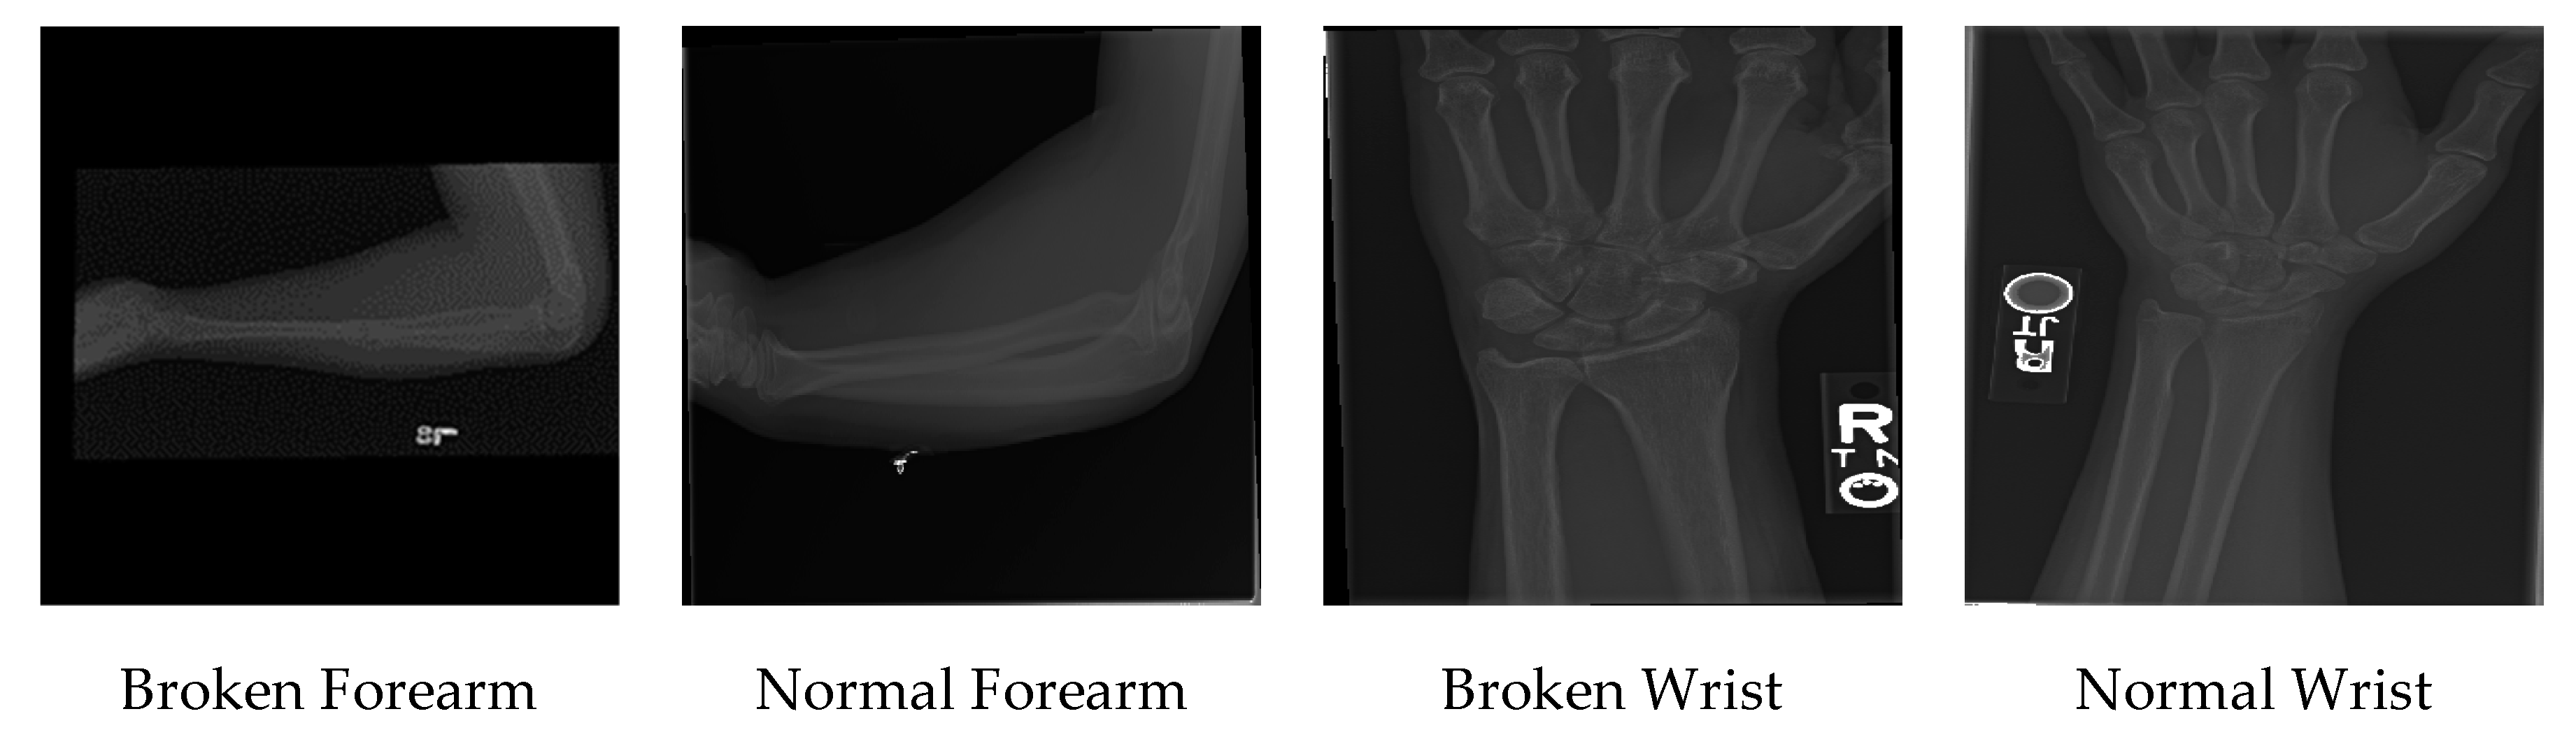

All in all, 92% of the dataset is used for training, and 8% of the dataset is used for testing the results. The summary of the dataset is presented in Table 1. A sample of the MURA dataset is presented in Figure 1.

Figure 1. A sample of the MURA dataset.